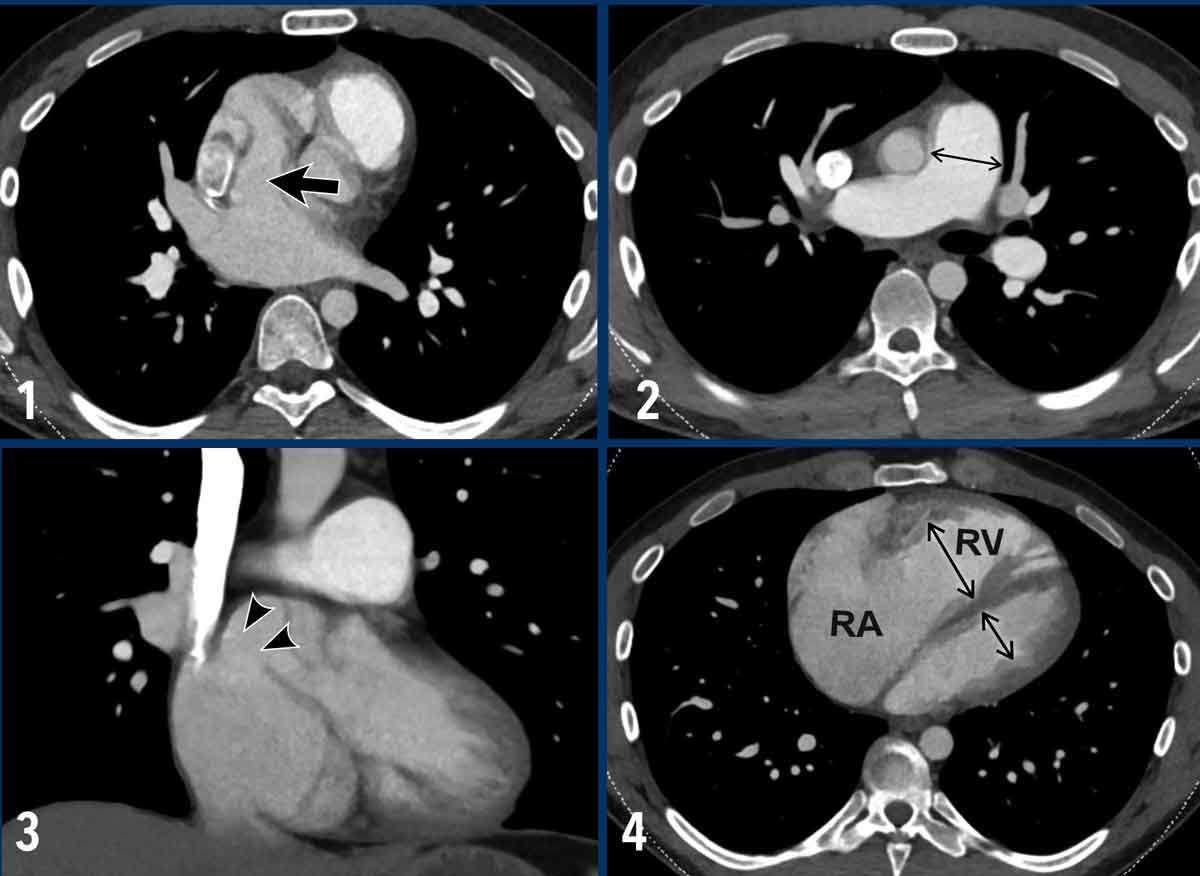

Atrial Septal Defect (ASD)

In an Atrial Septal Defect (ASD), there is a communication between the left and right atrium.

Since left atrial pressure is higher, blood flows from the left atrium to the right atrium.

This increases blood volume in the right heart and pulmonary circulation.

The chronically elevated flow and pressure in the lung circulation causes endothelial damage, vascular remodelling and an increased pulmonary vascular resistance.

Illustration

Example of a sinus venosus superior defect.

This is a subtype of ASD, in which there is an abnormal interatrial communication between the left atrium and the superior cavo-atrial junction (arrow).

Since this subtype of ASD frequently coexists with PAPVR, always check for both conditions.

Images

1. There is an abnormal communication between the left atrium and the superior cavo-atrial junction (arrow).

2.  Dilatation of the pulmonary artery.

3. Coronal reconstruction demonstrating the abnormal communication between the left atrium and the superior cavo-atrial junction (arrowheads).

4. Severe dilatation of the right atrium and ventricle due to the left-to-right shunt.